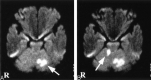

Fig 1.

Diffusion-weighted MR images. A, Diffusion-weighted image on day 1 shows a high-signal-intensity area in the left cerebellar hemisphere (arrow). B, Diffusion-weighted image on day 5 shows a new ischemic lesion in the right cerebellar hemisphere (arrow).